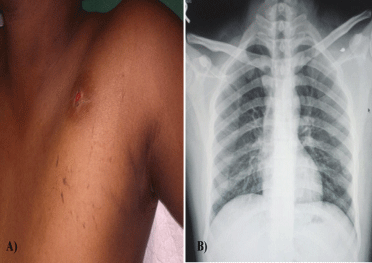

Subclavian Artery Pseudoaneurysm Secondary to Accidental Stone Chip Injury and its Excision

A pseudo aneurysm, also known as a false aneurysm, is a hematoma that forms as a result of a leaking hole in artery.